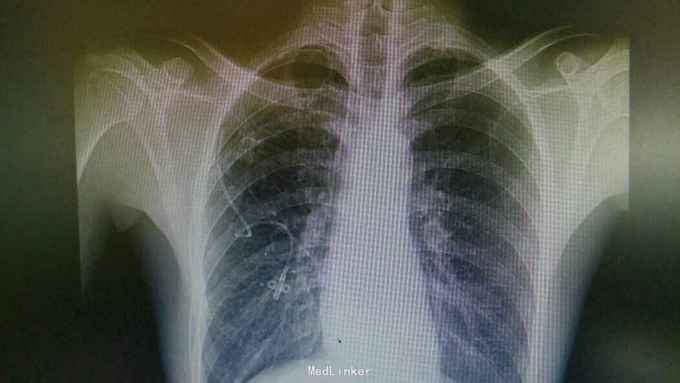

诊断:右肺气胸。 治疗:排除胸腔穿刺禁忌,予以闭式胸腔引流排气。后辅查胸片:右肺液气胸,压缩5%。